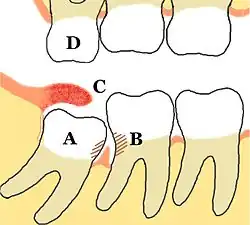

Some problems which may or may not occur with third molars: A Mesio-impacted, partially erupted mandibular third molar, B Dental caries and periodontal defects associated with both the third and second molars, caused by food packing and poor access to oral hygiene methods, C Inflamed operculum covering partially erupted lower third molar, with accumulation of food debris and bacteria underneath, D The upper third molar has over-erupted due to lack of opposing tooth contact, and may start to occlude into the operculum over the lower third molar traumatically. Unopposed teeth are usually sharp because another tooth has not blunted them.